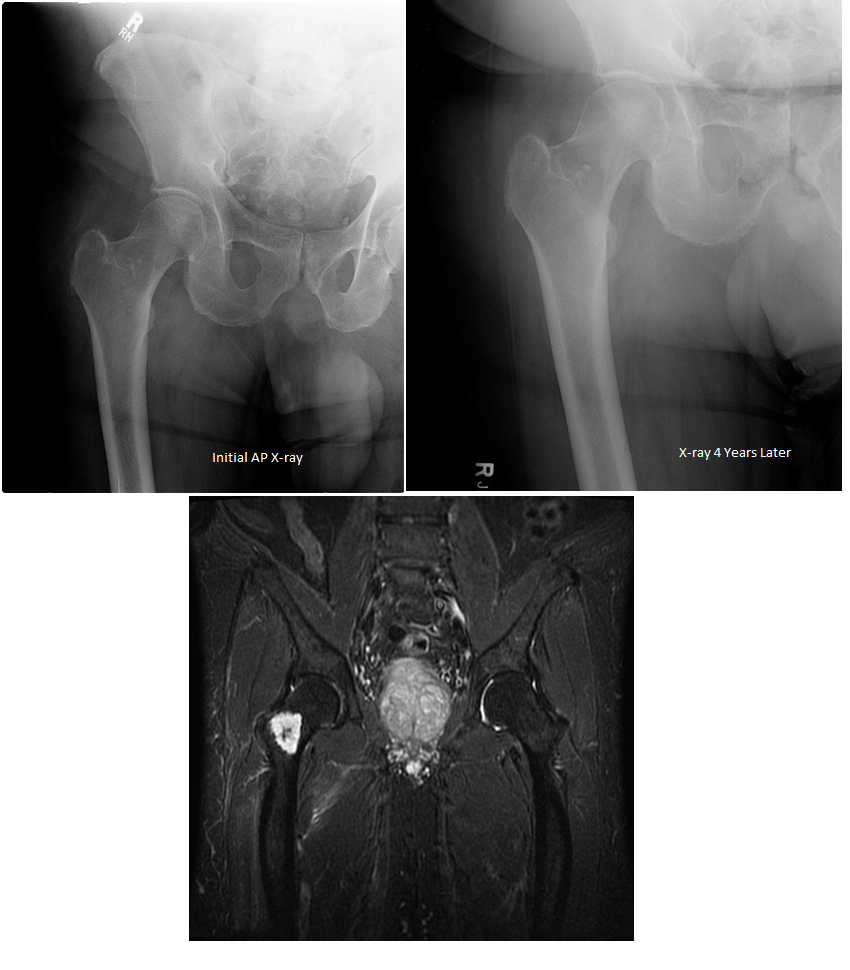

A 79-year old female presents with complaints of right hip pain for 2 months. She denies prior injury or precipitating event. The pain is made worse by lying on the affected side and occasionally hurts with hip motion. The pain is improved with NSAIDS and placing ice on the lateral aspect of her hip. Her primary care physician ordered x-rays which showed a bone lesion in the proximal femur. Her PCP was concerned she had bone cancer and ordered an MRI of the thigh to further evaluate. AP x-ray and a coronal MRI image are shown above. The patient denies a history of weight loss, fatigue, and history of cancer. On exam the patient has no pain with passive range of motion of the hip in all planes. She has pain with palpation over the greater trochanteric bursae. Motor and sensation are intact throughout the lower extremities. What is the most likely cause of this patient’s pain?